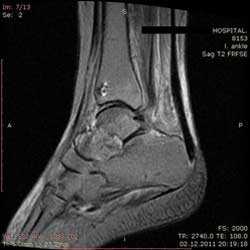

Рис4. а. на КТ перелом таранной и большеберцовой костей, б. на МРТ перелом таранной кости

Также с помощью КТ и МРТ возможно выявить не видное на обычных рентгенограммах повреждение хряща таранной кости.